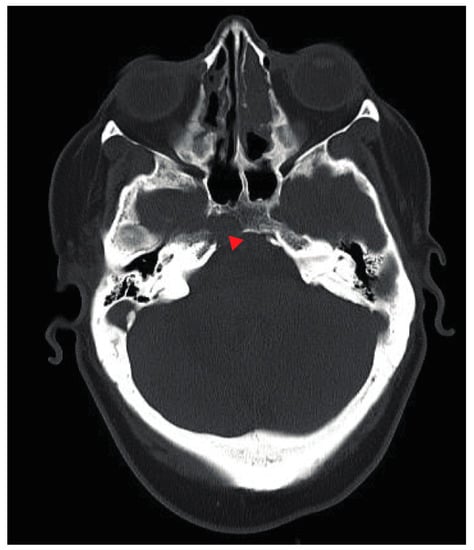

2. Case Presentation